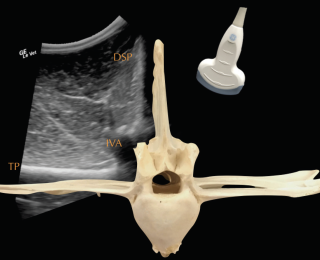

Deep to the ligament the fibrocartilaginous cap, visualised as a hypoechogenic line of approximately 1mm, is visible and runs parallel to the hyperechoic line of the DSP bone surface. The ISS cannot be assessed fully and a statement about potential iminging DSPs should not be made based on ultrasonography alone. The intervertebral articulations can be examined ultrasonographically, both in sagittal and frontal planes, using a convex transducer (Denoix 1999a; Reisinger and Stanek 2005).

The anatomy and ultrasonographic appearance of the joints change slightly from cranial to caudal. The mammillary process is more prominent in the thoracic spine and the joint is positioned further axial and closer to the DSP compared to the lumbar region. Signs of pathology in the intervertebral articulations (see Figure 4) include new bone formation and an enlarged outline of the facet (Denoix and Dyson 2003).